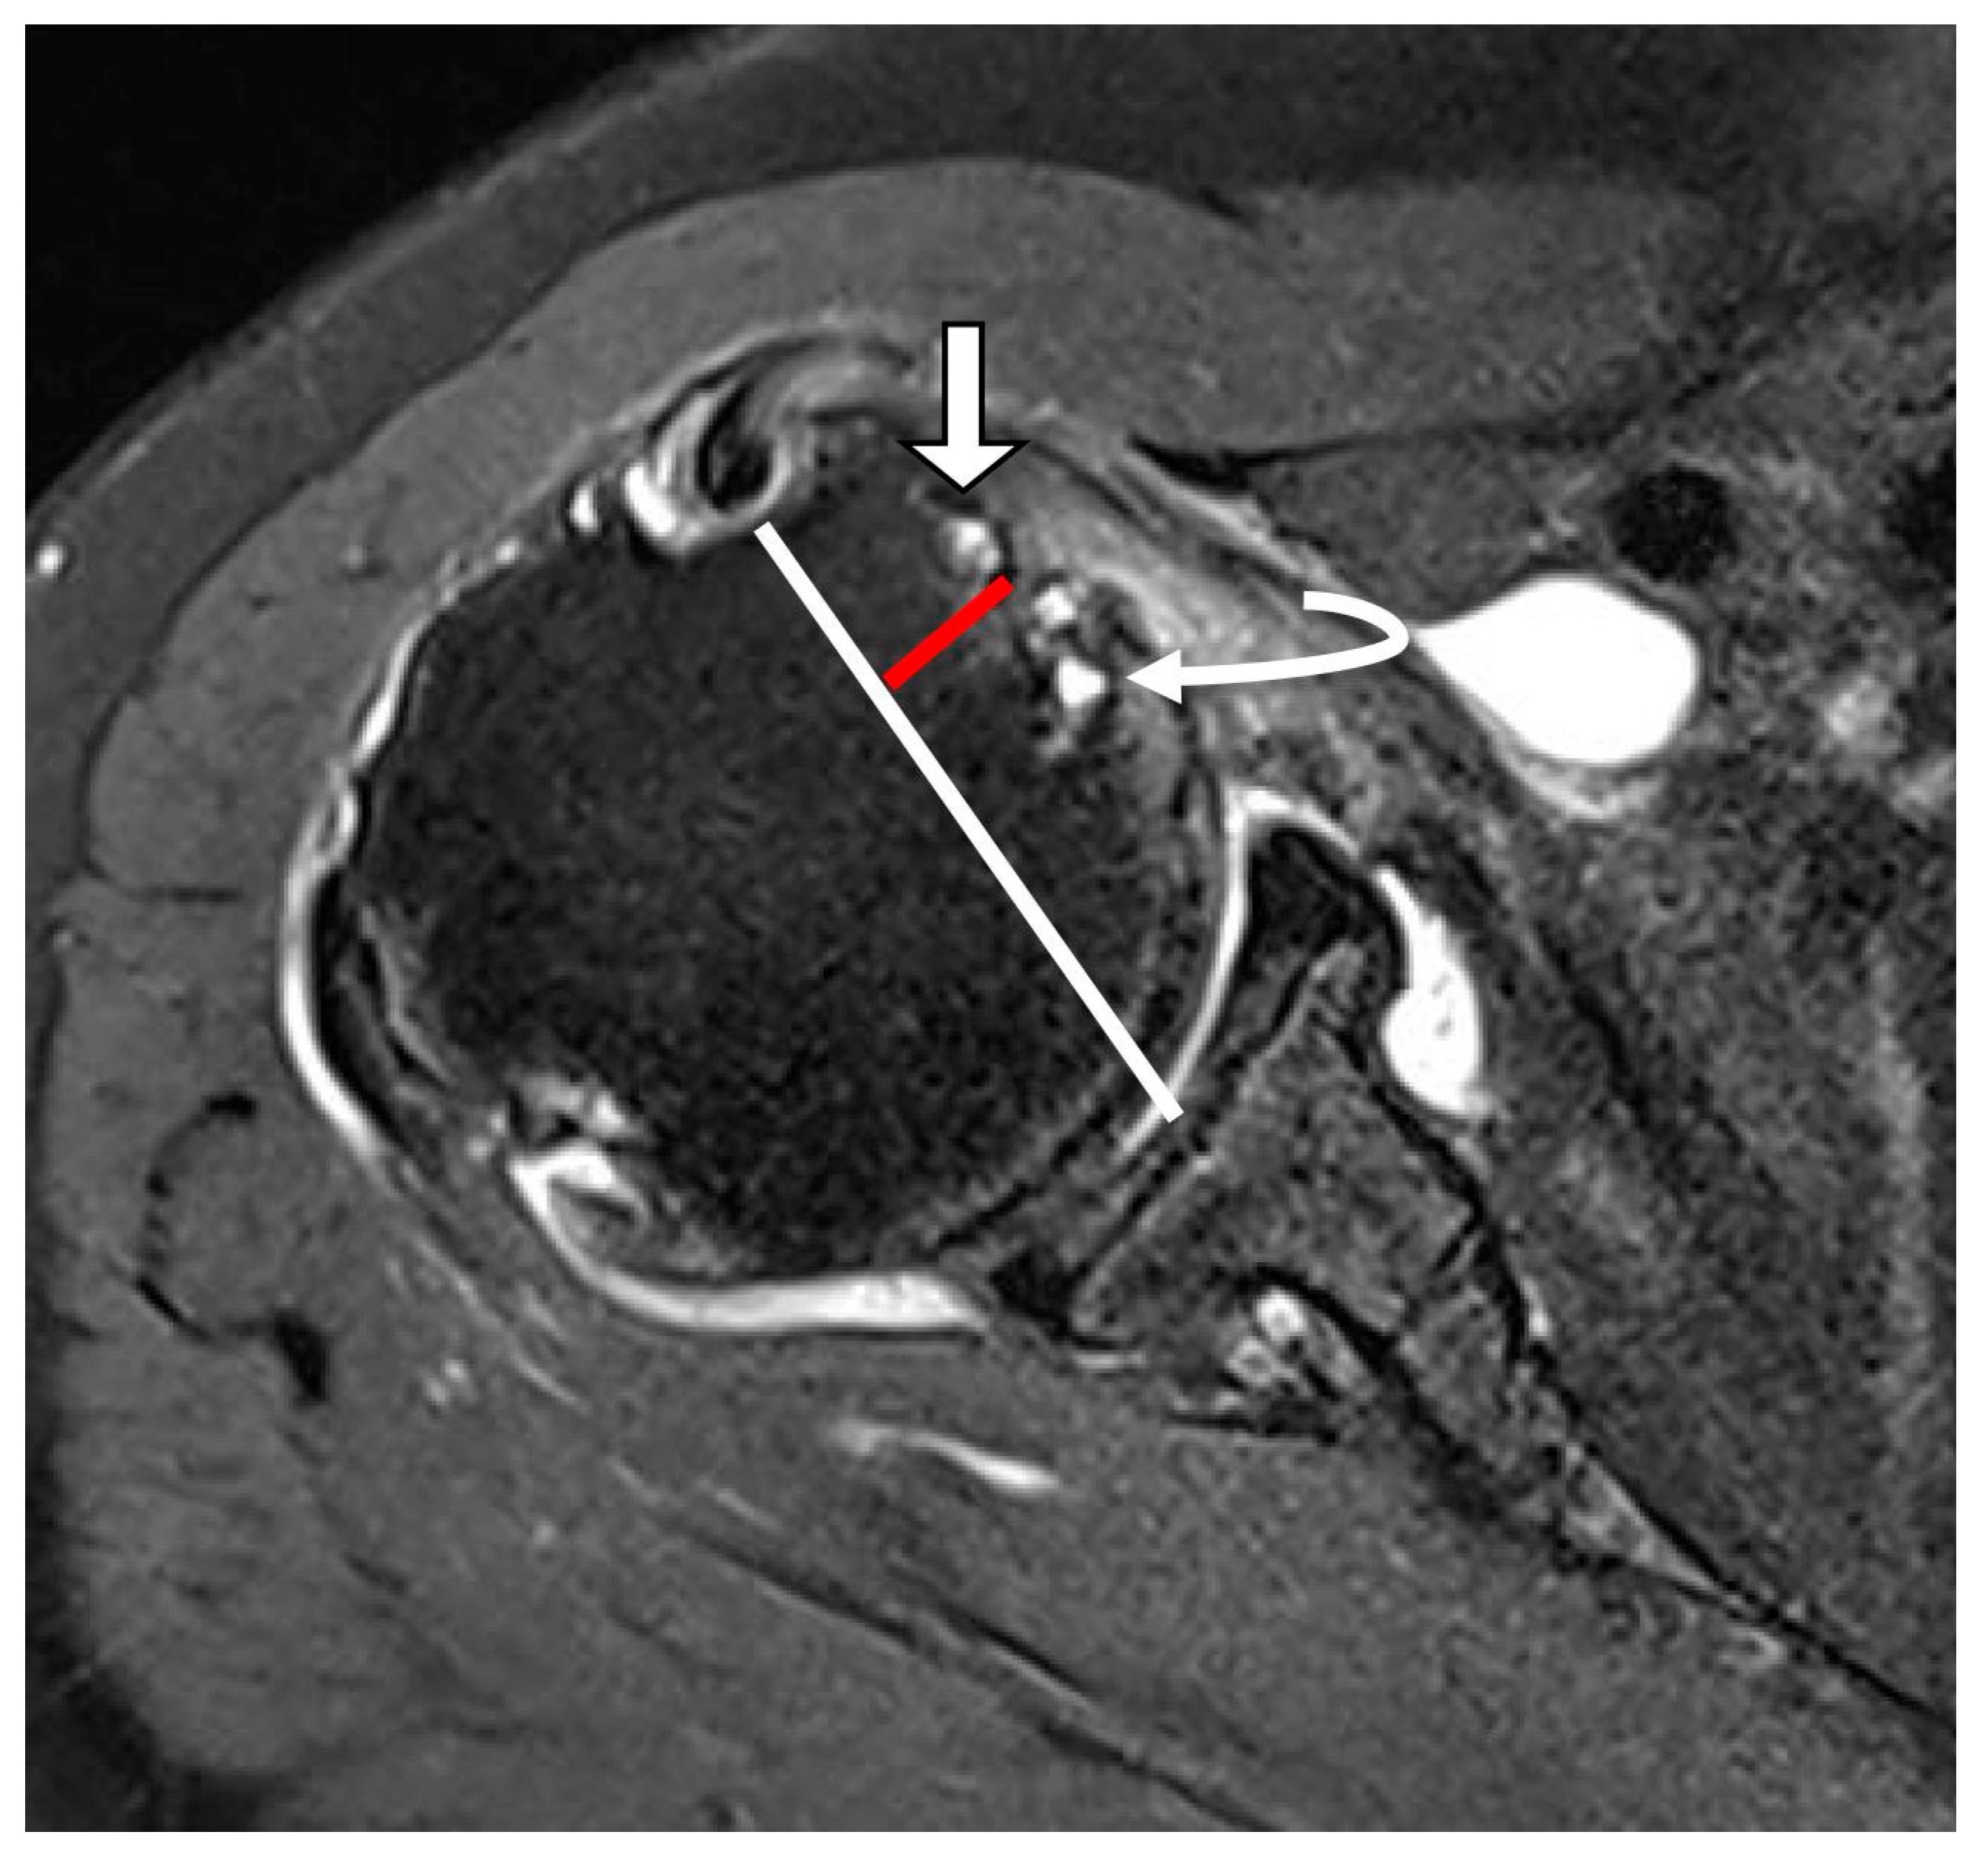

| Subluxation or dislocation (%) | 13 (12.1%) | 22 (81.5%) | <0.001 | κ = 0.853 (p < 0.001) |

| LHBT subluxation | 31.815 | 10.267–98.593 | <0.001 | 22.836 | 3.993–130.605 | <0.001 |